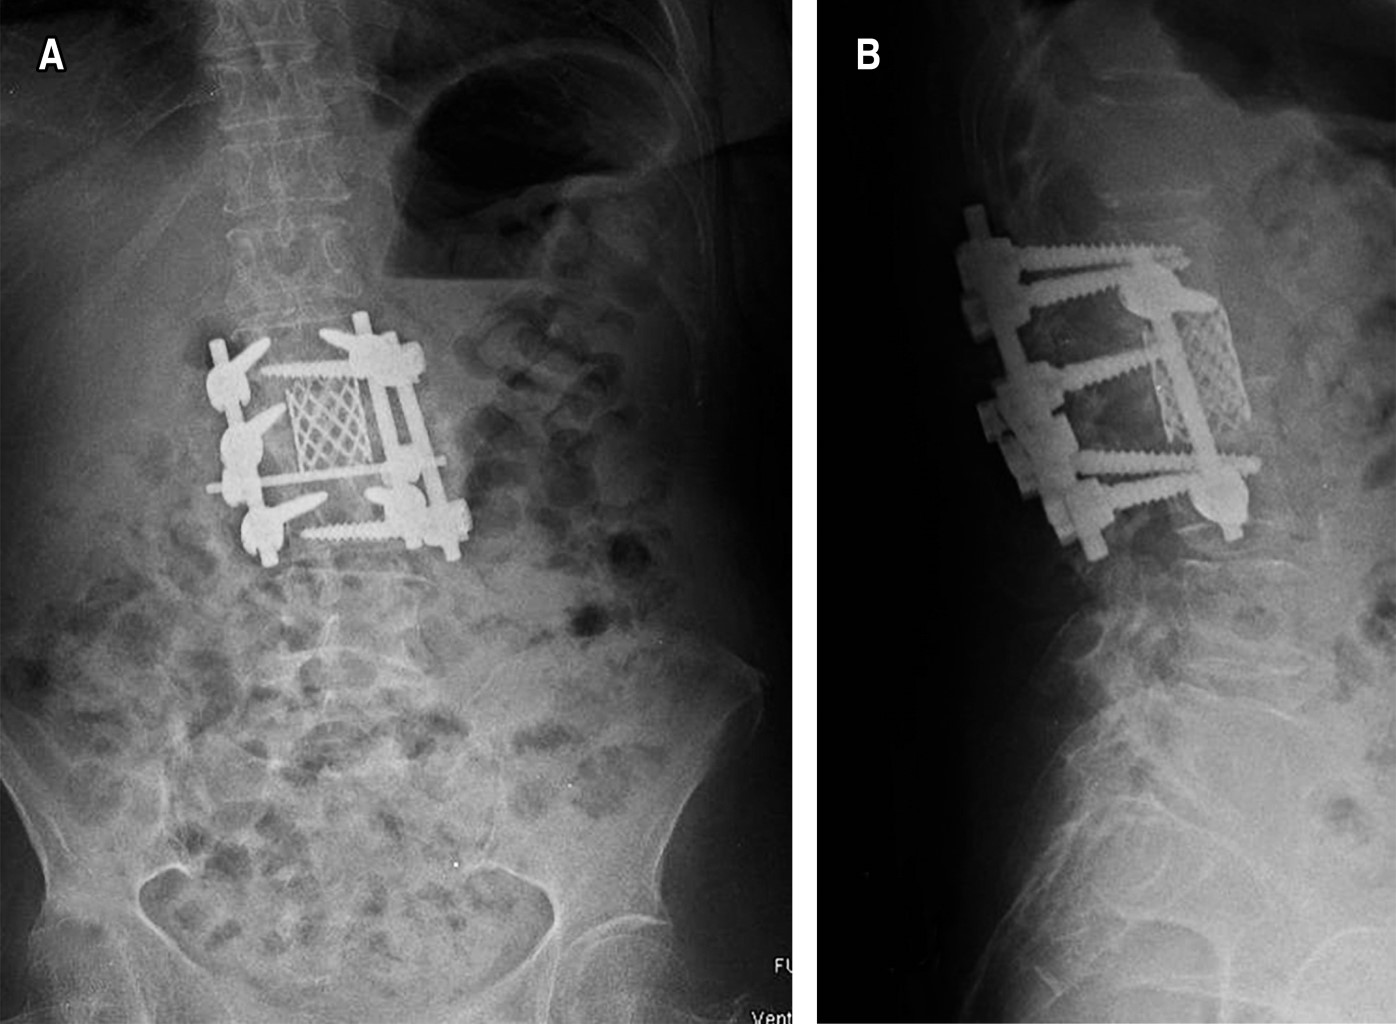

Introduction: brucellosis infection is considered a global public health problem, which is estimated in about 58% of the cases demonstrated with osteoarticular involvement. With a special predilection for involvement of the lumbar spine, in patients with carriers mostly with clear identifiable risk factors. Clinical case: we present the case of a 60-year-old female patient, who began suffering consistent with the presence of pain in the thoracolumbar region of long evolution, with poor response to conservative treatment which shows a progressive intensity, until conditioning loss of ambulation and prostration. A study protocol was performed, in which X-ray and computed axial tomography (CAT) were observed lytic lesion in the vertebral body L2, as well as hyperintense lesions with a tendency to invasion of the spinal canal in axial and sagittal T2 section. Conclusion: brucellosis continues to be an important pathology in our country, in our clinical case a surgical resolution similar to that reported in the international literature was performed, with the topic of the different tools available for such resolution.

Figure 3